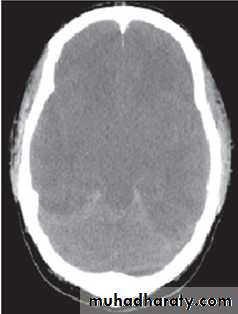

Cerebral Edema

• Cerebral edema is responsible for the majority of deaths related to DKA in children, and significant neurologic morbidity persists in many of the survivors.• While it typically presents 4 to 12 hours after treatment is begun, it can present later, or earlier, including before treatment is initiated.

• The cause of cerebral edema in DKA is not known, but there are some risk factors attributed to cerebral edema. These include:

• young age.

• Rapid fluid replacement & insulin infusion.

• Injudicious use of bicarbonate therapy.

• Severe presentation:

• pH < 7.2

• lower serum bicarbonate concentration

• higher serum glucose concentration

• higher blood urea nitrogen concentration

• hypernatremia

Clinical features

• severe headache.• sudden deterioration in mental status.

• bradycardia (or a sudden, persistent drop in heart rate not attributable to improved hydration).

• Hypertension.

• depressed respiration

• cranial nerve dysfunction.

• posturing, and seizures

• incontinence.

• Papilledema is a late sign.

• The 1st thing to be excluded is hypoglycemia.• Mannitol 0.5g/kg is infused over 30-60 min & can repeated if necessary.

• Fluid restricted to 2/3 maintenance & the total correction should made over 48-72hrs.

• If the patient requires intubation, hyperventilation should be avoided, as it has been shown to be associated with worse outcomes